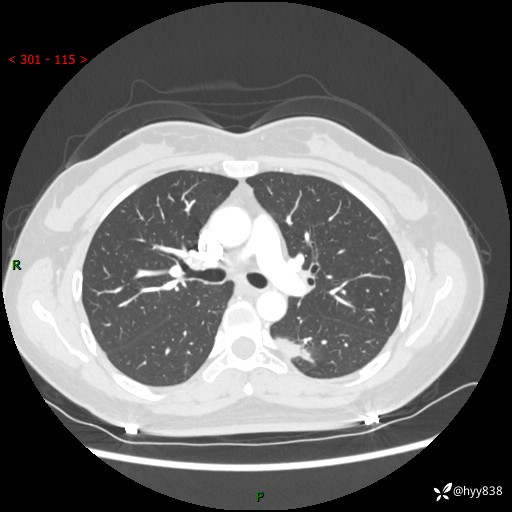

【患者信息】:36岁/女

【主诉】:左侧下胸部阵发性疼痛2周,乏力1周

【现病史及既往史】:患者自诉2周前饮酒后出现左侧下胸部阵发性疼痛,不随呼吸改变,无咳嗽咳痰、头晕头痛、咳血、呼吸困难等不适,于当地第一人民医院查胸部CT提示肺部感染,随后前往我院门诊给予抗感染(左氧氟沙星)治疗1周,自诉胸痛较前好转,感乏力、头晕,偶尔干咳,无咳痰,无发热、畏寒、胸闷、咯血、四肢酸痛、腹泻、腹痛等不适,门诊复查胸部CT提示:左肺下叶感染,病灶较前增加增大,遂以“肺部感染”收入我科。 起病以来,患者精神、饮食、睡眠可,大小便正常,体力体重无明显变化。

【检查】:胸部CT增强(外院平扫)